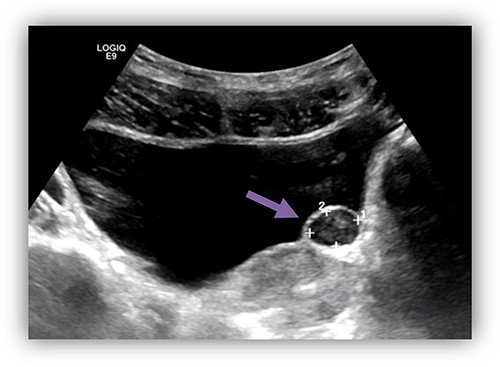

In a university hospital, we recently treated a 34-year-old gentleman who presented to urology clinic complaining of repeated episodes of dysuria and incomplete voiding for the last 3 months. During the initial evaluation, no abnormalities were found on physical examination or in routine laboratory studies. Ultrasound of the abdomen and pelvis (Fig. 1) showed a hyperechogenic cystic fluid-filled mass over the area of left vesicoureteric junction measures of 15 mm × 11 mm with no intraluminal lesions or debris. These findings are suggestive for left ureterocele. Pre-void volume of 257 ml, post-void volume of 22 ml and prostate size of 17.7 ml. No hydroureteronephrosis.

US bladder showed a cystic fluid-field bladder mass of 15 mm × 11 mm over the area of left vesicoureteric junction suggestive of left ureterocele.